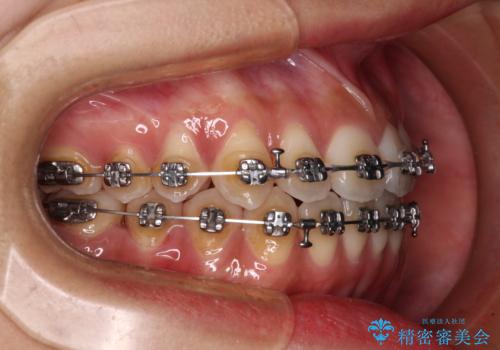

受け口と開咬を急速拡大装置とワイヤー装置で改善

- メタルブラケット

- 前歯の開咬と、受け口による咬み合わせの悪さを気にして来院された患者様です。

上顎歯列が狭窄していたため、急速拡大装置により上顎骨を側方に拡大し、その後ワイヤー装置にて矯正治療を行うこととしました。